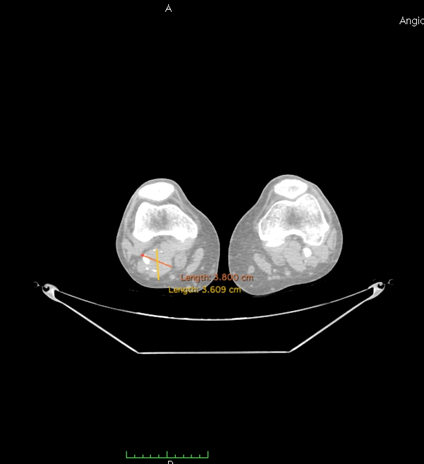

A 69 year-old male patient, with hypertension and post-operative of gastric bypass surgery for obesity, was admitted with right limb pain, mainly in the calf, associated with a weakness and difficulty walking, likewise a claudication symptom. On physical examination, he had a good general health, with a pulsating bulge with fibroelastic consistency palpable in the right popliteal region. The patient had femoral, popliteal and distal pulses present bilaterally. The patient was submitted to a duplex ultrasound, that suggested a popliteal artery aneurysm, with 3,8 cm diameter with thrombi and then was submitted to a computed tomography angiography (CTA) of the abdomen, pelvis and inferior limbs bilaterally. The CTA showed no other abnormalities in the arterial system, except for an isolated right popliteal artery aneurysm, with 3,8 cm diameter and thrombi associated. (Figure 1). The distance between the end of the popliteal artery aneurysm and the knee joint interline was 1,1cm. The proximal landing zone had 8,4mm diameter and distal landing zone had 6,7mm diameter. The total length of the PAA was 7,67cm. The patient was submitted to a duplex ultrasound in order to evaluate the great saphenous vein diameter, and it was inadequate for a open bypass, due to diameter < 3mm>

Figure 1: Angio-CT scan in axial incidence showing popliteal artery aneurysm (PPA).